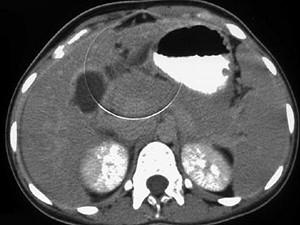

问题 女,45岁,急性右上腹剧痛2小时,向右肩放射,影像检查如图,应诊断为 ( )

选项 A、胆囊腺肌增生症 B、胆道梗阻 C、慢性胆囊炎 D、胆囊穿孔 E、急性胆囊炎 单选题

答案 D